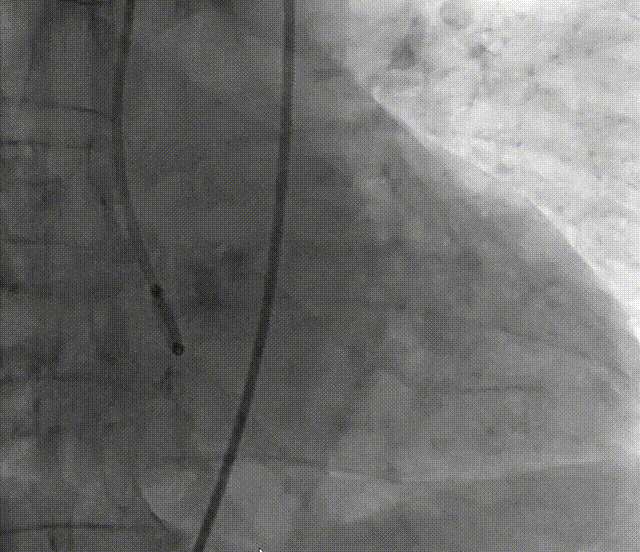

4. 双侧冠脉造影;

5. 右窦中心投照体位行主动脉根部造影;

6. AL2导管配合直头导丝跨瓣,交换加硬钢丝于左心室;

7. 22mm球囊预扩张;

8. 25mm Silara主动脉瓣膜过弓、跨瓣及定位;

9. 25mm Silara主动脉瓣膜左心室初步释放,瓣膜功能良好(不需要左心室快速起搏);

10. Silara 主动脉瓣膜提拉至瓣环水平,精准定位瓣膜,造影剂显示瓣膜功能良好,完成固化;

11. 最终造影瓣膜位置理想,无返流及瓣周漏。